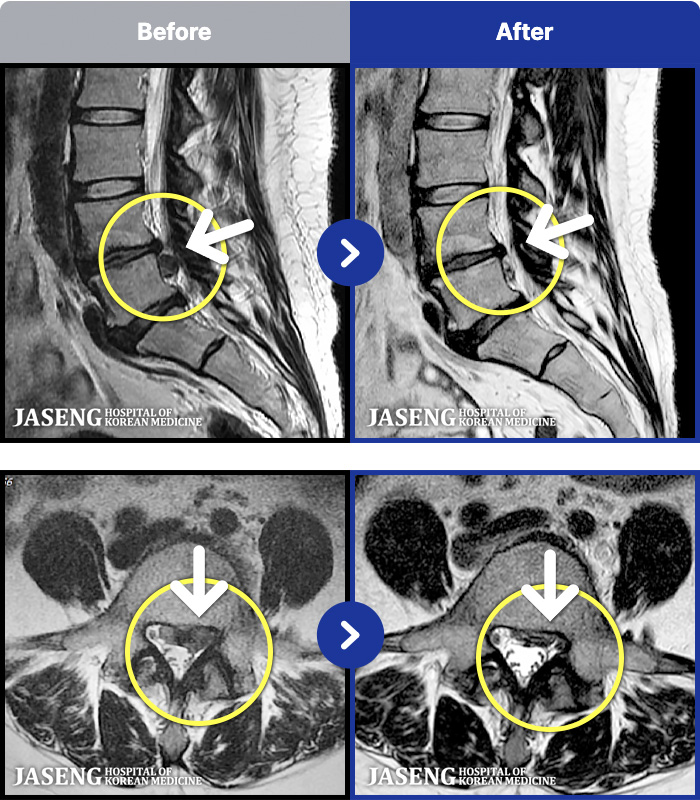

MRI ũ ʸ Ȯϼ.